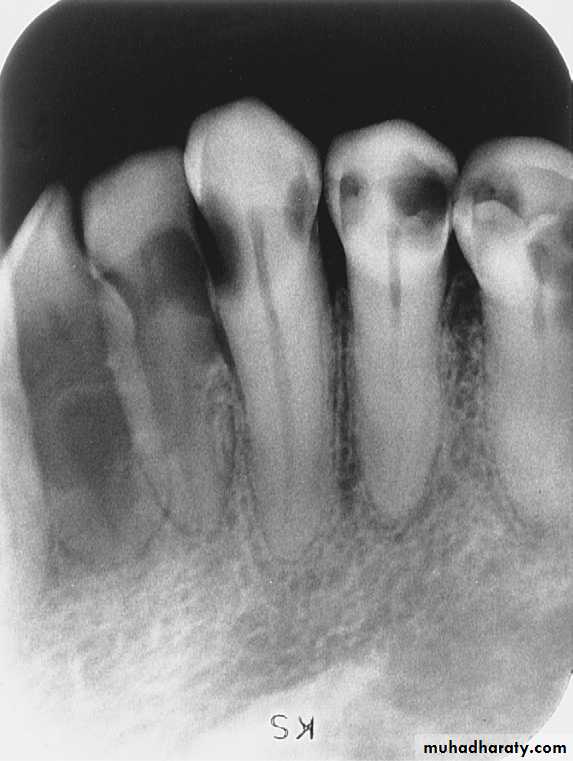

Rampant CariesRampant caries is advanced and severe caries that affects numerous teeth

Rampant caries is typically seen in children with poor dietary habits or in adults with decreased salivary flow.